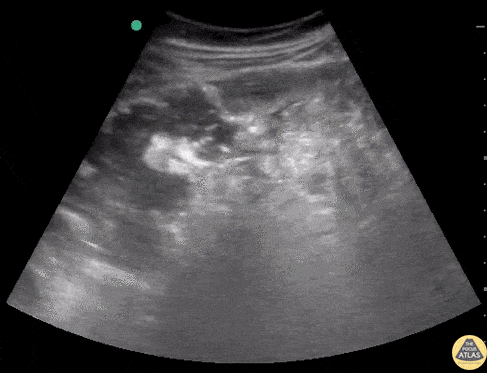

Bowel-GI - Perforated Appendicitis

30 y/o F with chills, constipation for 3 days. Normal labs and vitals, but distinctly tender in the RLQ. POCUS revealed free fluid and surrounding bowel wall edema with a structure floating that is likely the appendix. CT confirms a perforated appendix with trace free air complex fluid and thickening of the adjacent bowel wall. Dr’s Sophia Sharifali, Esther Kwak, and John F Kilpatrick - Kings County/SUNY Downstate Emergency Medicine